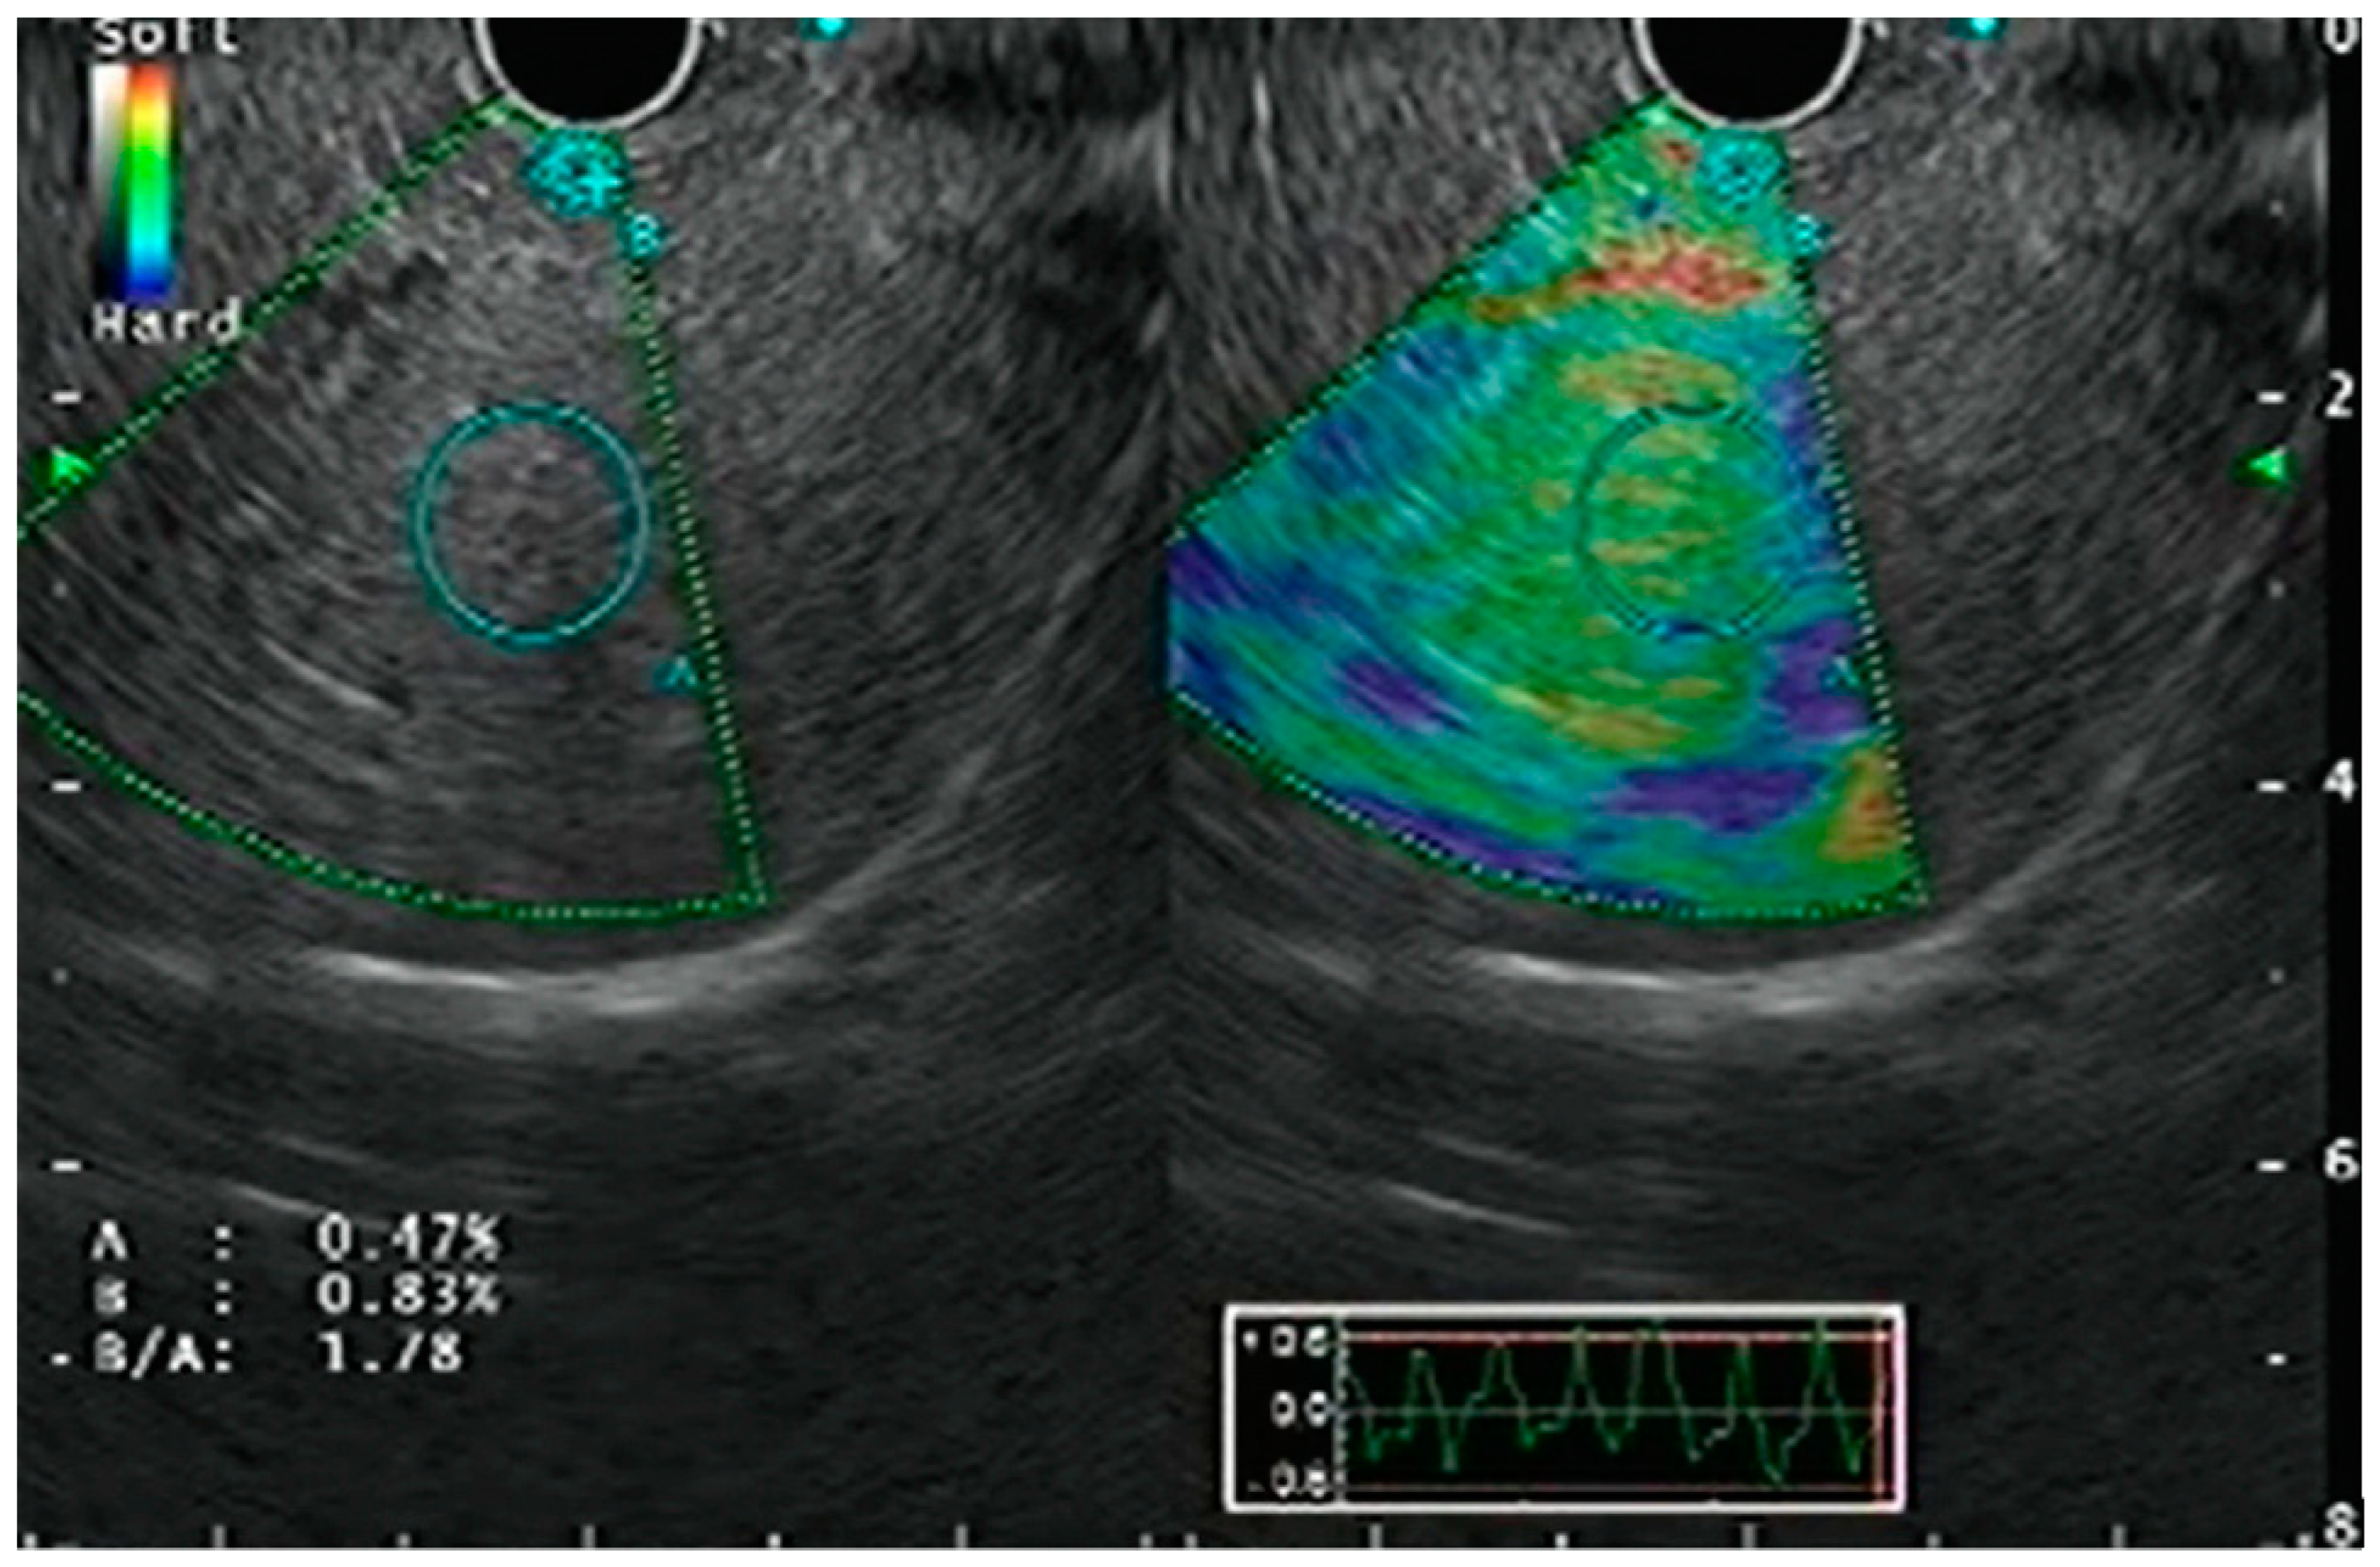

3.1. Strain Elastography